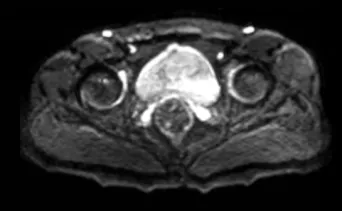

近日,我院泌尿外科再次为一名血精患者行精囊镜检查术。患者为42岁男性,一月来发现精液带血,甚至血尿,曾多方求医,均未见好转,遂来我院就诊。入院后完善核磁检查提示:双侧精囊腺异常信号影,初步诊断为精囊炎。

经科室医师团队讨论,考虑为顽固性血精,射精管梗阻,在副院长、泌尿外科主任医师李朝明的带领下为该患者实施了精囊镜检查手术。

术中,采用4.5~6.0F精囊镜,经尿道进镜后,观察到精阜两侧射精孔开口极其细小,成功插入斑马导丝后,钬激光切开射精孔,置入精囊镜,发现患者精囊腺内悬浮浑浊物,内有血块,反复冲洗精囊囊腔。手术顺利,术后无血精出现,患者恢复良好,现已出院。